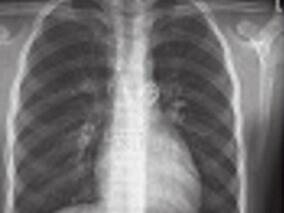

1小时条评论特发性肺动脉扩张(IDPA)是一种比较少见的疾病,一般不需要治疗,预后良好。由于许多先天性和获得性心血管疾病均可引起肺动脉扩张,容易误诊,因此,正确鉴别IDPA和继发性肺动脉扩张有重要的临床意义。 【临床资料】 患者,女,20岁,因咳嗽、心悸2年入院。患者2...